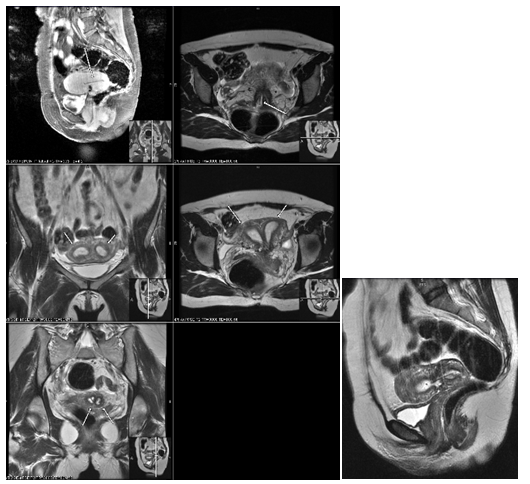

A 15-year-old Hispanic female, G0P0, initially presented with persistent sharp right lower quadrant pain. The patient was treated for pelvic inflammatory disease but, during further evaluation to rule out ovarian cyst and ovarian torsion, the patient was discovered to have severe primary dysmenorrhea, MDA and a solitary kidney. Ultrasound (Figure 1) and magnetic resonance imaging (MRI) (Figure 2) revealed a uterus didelphys with obstructed Hemivagina and Ipsilateral renal agenesis (OHVIRA syndrome) also known as Herlyn-Werner-Wunderlich Syndrome (Figure 3). Ultrasound indicated a 7.1 x 7.0 x 7.2 cm thick-walled right adnexal structure containing debris and fluids, which represented uterine didelphys with hematometra of the right-sided uterine horn (Figure 1 & 2). There was also a left uterine horn, which was oriented in the left pelvis and appeared unremarkable. Initial reproductive endocrinology and infertility recommendation was for 6 months of Leuprolide (Lupron) followed by continuous oral contraceptives (OCP) (with no placebo week), which the patient completed. However, the patient started getting her menstrual period every month (heavy and painful) while on OCP. The OCP was stopped and once the bleeding stopped the patient was re-started on 6 months of Lupron with norethindrone add back therapy, followed by continuous OCP (with no placebo week). The patient is currently scheduled to discuss the surgical option of hemi hysterectomy of the right rudimentary uterus versus resection of vaginal septum to open of obstructed Hemivagina.10

Figure 2 Patient 1: Pelvic MRI: A normal-appearing uterine horn is seen in the left pelvis measuring 4.2 x 1.7 x 2.1 cm. A 9.7 x 4.9 x 4.7 cm lobular tubular thick wall cystic structure in the right pelvis is seen. Signal intensity suggests hemorrhagic contents. This lesion is contiguous with a similar but smaller dilated tubular structure extending to the right aspect of the posterior vagina. Findings are suspicious for uterine didelphys with hematometra of the right-sided uterine horn and cervix.

Figure 3 Patient 1: MRI of Abdomen with and without Contrast: Showing normal left kidney (Red Circle) with Right Renal Agenesis

In all three cases pelvic ultrasound was initial imaging tool. The ultrasound in case 1 (Figure 1) and subsequent MRI (Figure 2) shows a lobular tubular thick wall cystic structure in the right pelvis suggesting hemorrhagic contents extending into the right aspect of the posterior vagina and didelphys uterus. MRI of the abdomen depicts renal agenesis, demonstrating abnormal kidney development confirming HWW. As per the classification presented by Zhu and imaging, the patient has a class 1.2 OHVIRA.2 The ultrasounds in cases 2 and 3 (Figures 6 & 9 respectively) both demonstrate didelphys uterus with two cervices. The additional MRI in case 2, revealed two separate cervices and two uteri one with a retained IUD. MDA can be associated with a vaginal septum, more commonly vertical (Case 2 & Figure 5) but cases of a horizontal septum have also been reported (Case 1 & Figure 8).14